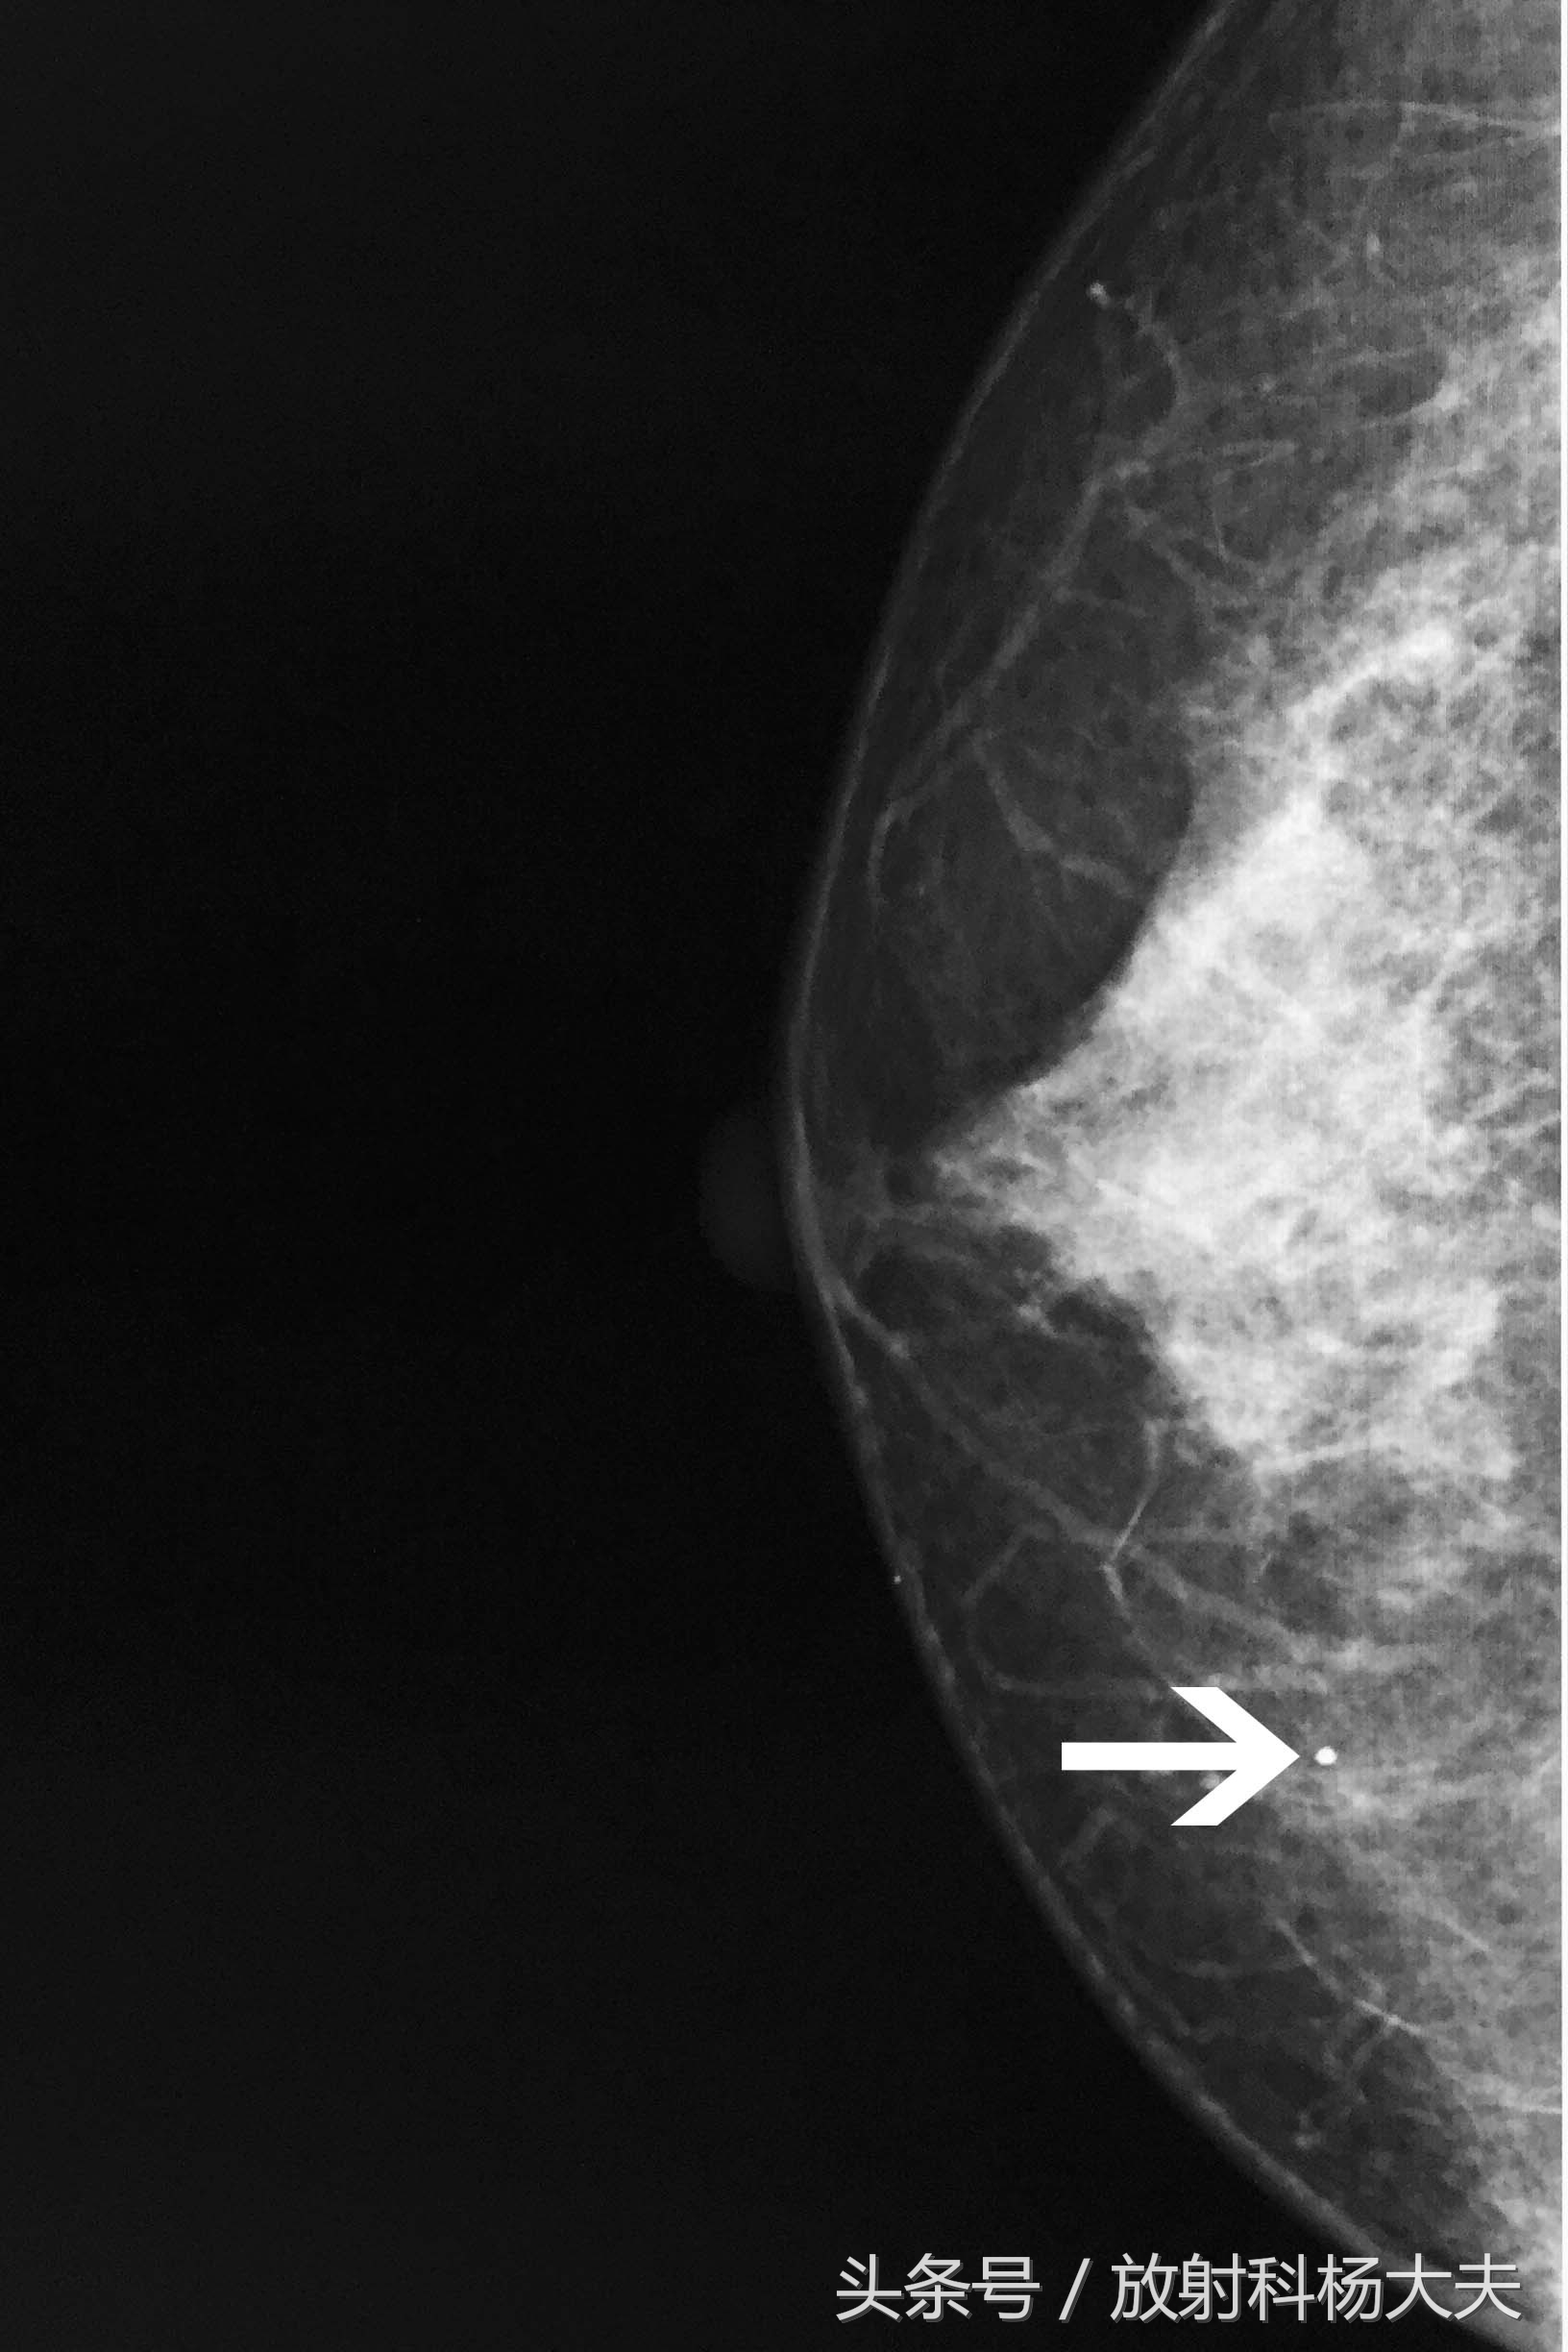

而她朋友的片子是这样的(图二):

而恶性钙化形态多呈细小砂粒状、线样或线样分支状,大小不等,浓淡不一,常密集成簇或呈线性走行及段性分布。如上图 2。除了钙化本身,还要看钙化伴随的肿块有无,肿块形态等等。

如上所述:这位女粉丝的乳腺钼靶图像中可见一枚粗大点状钙化灶,密度较高,这种多为良性钙化,而她朋友的钙化则倾向于恶性,大小不等、浓淡不一、密集成簇分布,这种情况则需积极治疗了。